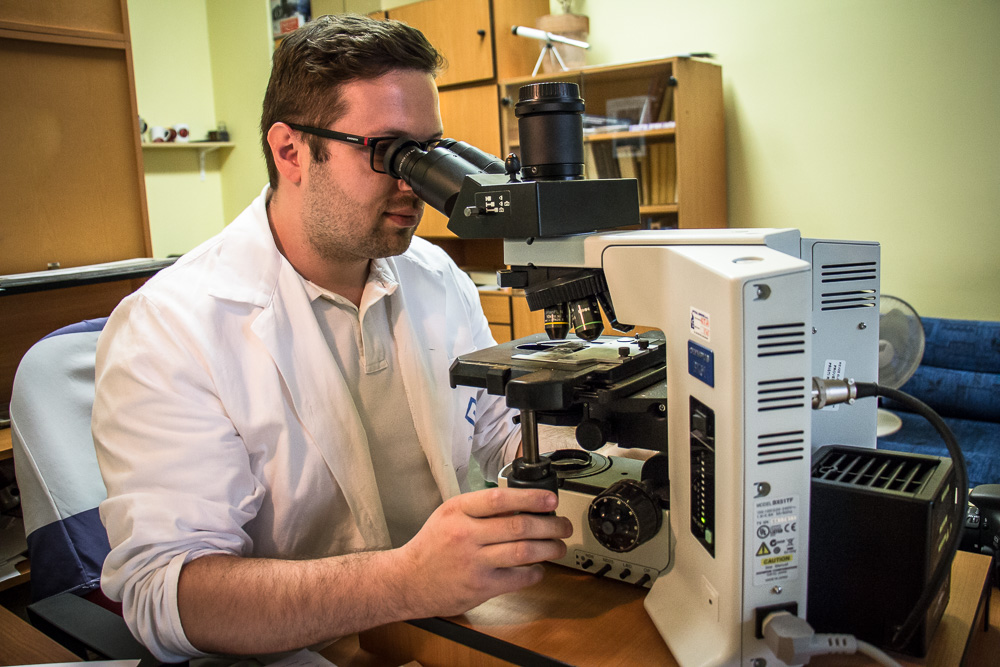

Ústav patologie a molekulární medicíny se zabývá komplexní laboratorní diagnostikou nádorových a nenádorových onemocnění. Využívá metod klasické histologie a cytologie s navazujícími dalšími speciálními laboratorními vyšetřovacími metodami. Ty zahrnují: pohled do buněk a tkání na úrovni ultrastrukturální analýzy (elektronová mikroskopie), průkaz exprese proteinů (metody imunohistochemické, Western blot, průtoková cytometrie), průkaz enzymové aktivity ve tkáňových řezech (enzymová histochemie), analýzu změn na úrovni chromozómů a genů a průkaz některých virů v histologickém řezu (metody in situ hybridizace) a rozbor DNA a RNA extrahovaných ze tkání (metody kvalitativní a kvantitativní polymerázové řetězové reakce, sekvenování). Vyšetřovaným biologickým materiálem jsou tkáně (nativní, zmrazené, fixované), punktáty kostní dřeně, periferní krev, případně jiné buněčné tekutiny (výpotky) a autologní štěpy pro transplantaci kostní dřeně.

Diagnostikou onemocnění různých systémů se zabývají týmy školených pracovníků – lékařů a biologů s pomocí laborantek ve specializovaných laboratořích.